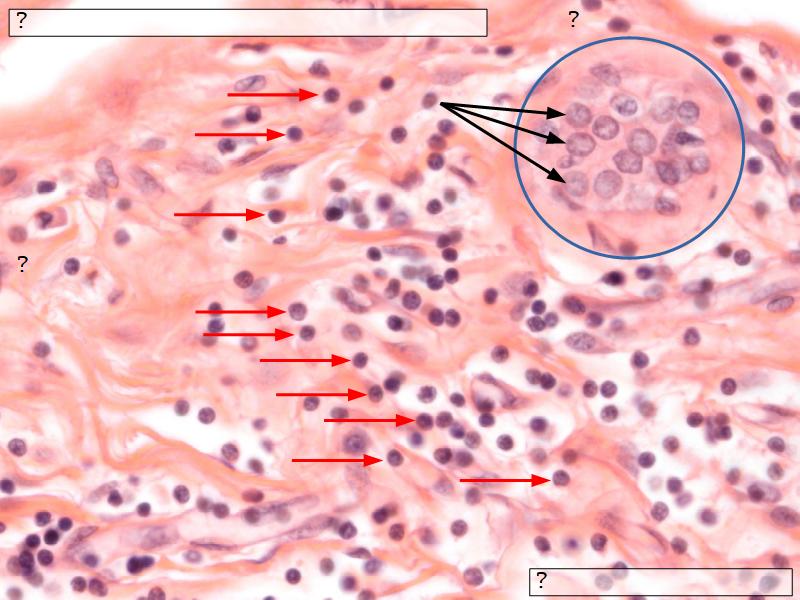

Mammary gland

Write short notes describing the structure of the mammary gland.

- Compound tubuloalveolar gland

Resting and active

Describe the resting mammary gland and compare with the active gland.

(8)

Resting gland

- Connective tissue dominate

- More adipose tissue

- Glandular tissue reduced

Active gland

- Terminal ducts expand

- Forms alveoli

- Connective tissue reduced

- Adipose tissue reduced

- Glandular tissue dominate

Structures

List the structures and cells found in the mammary gland.

Active gland

- Much larger than resting phase

- Terminal ducts proliferate to form alveoli

- Alveoli

- Surrounded by incomplete myoepithelial cells